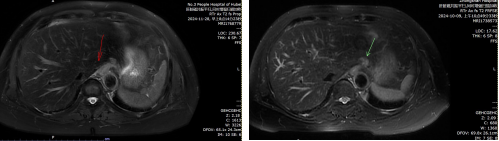

抱着最后一丝希望,曾阿姨和家人辗转来到武汉,找到了该院肿瘤血液科主任孙建海。孙建海主任详细了解了曾阿姨的病情,并进行了全面的复查。复查结果显示曾阿姨存在肝脏转移。经过院内会诊和科室讨论,考虑到曾阿姨之前多次手术和化疗,身体状况已无法耐受全身化疗和免疫靶向治疗,专家团队决定采取备选方案,先对肝脏转移病灶进行放疗,待放疗结束后再劝导曾阿姨接受全身治疗。

放疗结束一个月后,曾阿姨来院复查,结果显示,肝脏部位接近两公分的转移灶已经消失。“奇迹似乎真的在慢慢发生!”曾阿姨的女儿激动地说,“与之前的手术治疗相比,放疗的副作用明显小了很多。我妈妈不再像手术后那样,被疼痛和虚弱折磨得无法正常生活。她的身体逐渐有了一些力气,也能吃下一些东西了!”看着身体状况逐渐好转,曾阿姨对未来的抗癌之路重新燃起了希望。